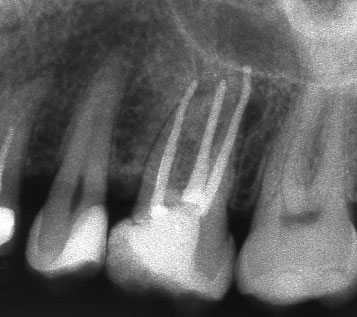

Ако при диагностична рентгенография се установи, че даден канал не е запълнен до физиологичното стеснение, е необходимо да се проведе повторно ендодонтско лечение.

В някои случаи недобре запълненият коренов канал е показание дори за отстраняване на протезни конструкции (корони и мостове) в които е включен съответният зъб.

Понякога е налице патологичен процес около апекса на зъба, който налага да се проведе допълнителна хирургична намеса с цел отстраняване на лезията.